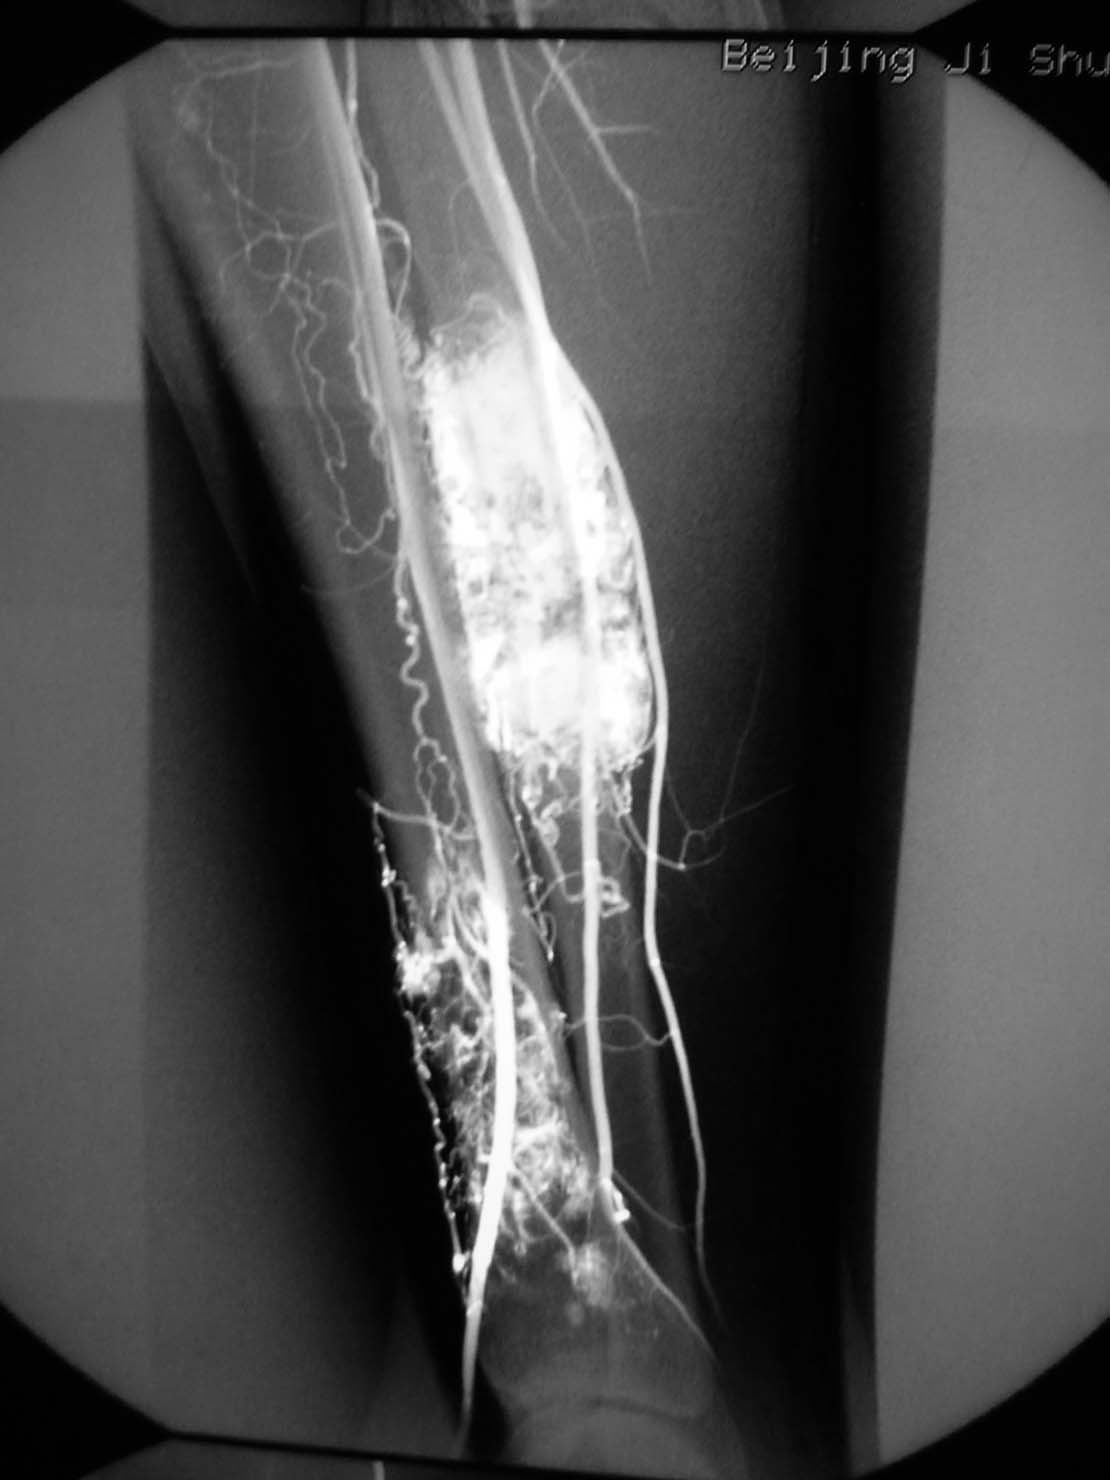

病理结果,腺泡样软组织肉瘤!

腺泡样软组织肉瘤

极为罕见,其组织来源不明。

起源于肢体软组织者称腺泡状软组织肉瘤,原发于骨内者,称骨腺泡状肉瘤。

本病大多发生于股部、臀部及小腿深侧肌群,上肢和其他部位少见。

x线平片:圆形或卵圆形软组织肿块影,基底部与病骨相连。

肿瘤内可见斑点状或细小结节状钙化。

骨质破坏大多表现为溶骨性地图状或虫噬性破坏,并常伴有层状骨膜反应。

mr检查:t1和t2加权像均显示肿瘤组织呈分叶状高信号强度,并见肿瘤内有低信号间隔。